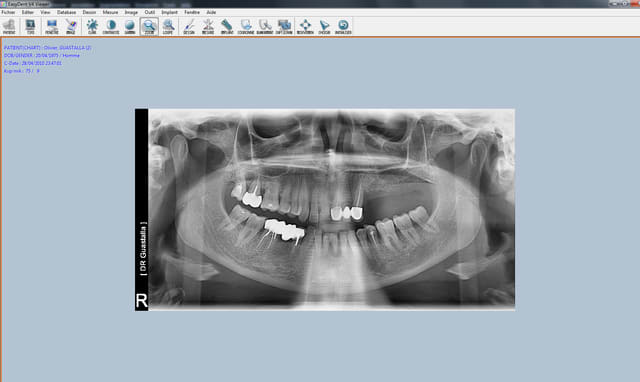

Bon finalement j'ai fait mon choix, cone beam installé hier !

Vatech Ewoo.

Pour moi les plus :

- taille de champ variable: 5*5 8*5 8*8 12.5*8

- vraie combo pano/cone beam

- interface sympa

- artefact métallique limité

- Logiciel d'imagerie et planification implantaire très bien

(pour info c'est une version d'Ondemand3D à l'essaie pour 90j ici:

http://www.ondemand3d.com/Content/Download/Trial.aspx prix du soft environ 5000$)

- budget compétitif

quelques clichés d'essais